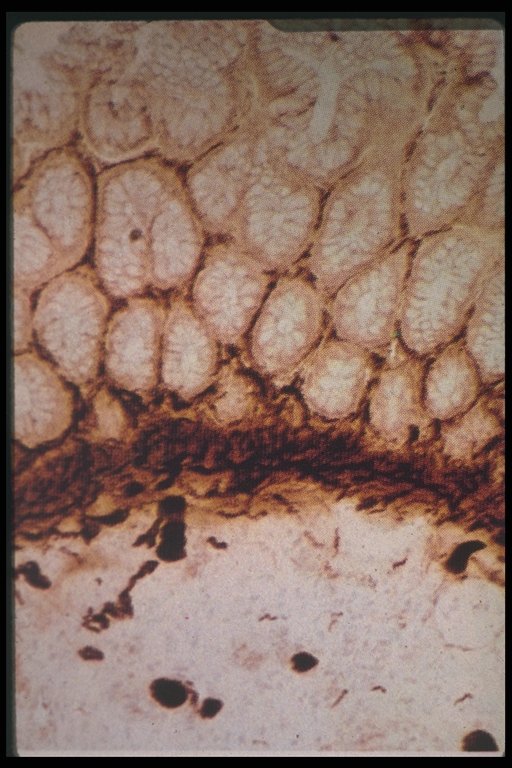

Increased acetylcholinesterase activity in Hirschsprung's disease, thick staining is observed in mucosa and submucosa layer